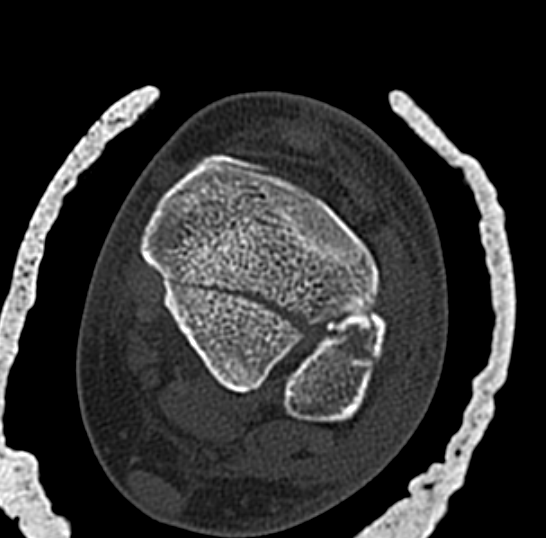

Posterior Malleolar Fractures

- occult in 70%

- especially with spiral distal tibial fractures

Wang et al. J Orthop Surg Res 2021

- systematic review

- incidence 70% occult fractures